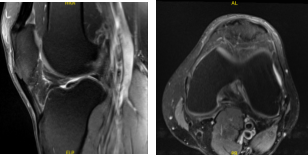

The patient presented MRI results that showed mild to moderate insertional quadriceps and proximal patellar tendinosis. There is prominent spurring along the inferior pole of the patella without a separate ossific fragment or surrounding bone marrow edema indicative of previous traction injury.

No meniscal tear or ligament injury. Cartilage is preserved. For the right knee, the X Ray results have shown Shallow undersurface tear at the posterior horn/body junction of the medial meniscus and undersurface fraying of the posterior horn.

MRI-3T Left Knee non-contrast

MRI-3t Right Knee non-contrast